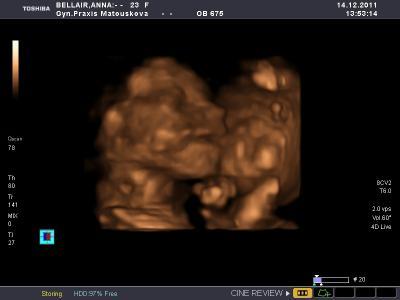

3 D Foto unserer Maus

Habe den Beitrag eben ins allgemeine Forum gepostet... Wollte euch mal ein 3D Bild unserer süßen Maus zeigen. Bin so verliebt Habt ihr auch 3D machen lassen?? LG Anna mit Krümeline

Bild zu 3 D Foto unserer Maus - Forum für April - Mamis